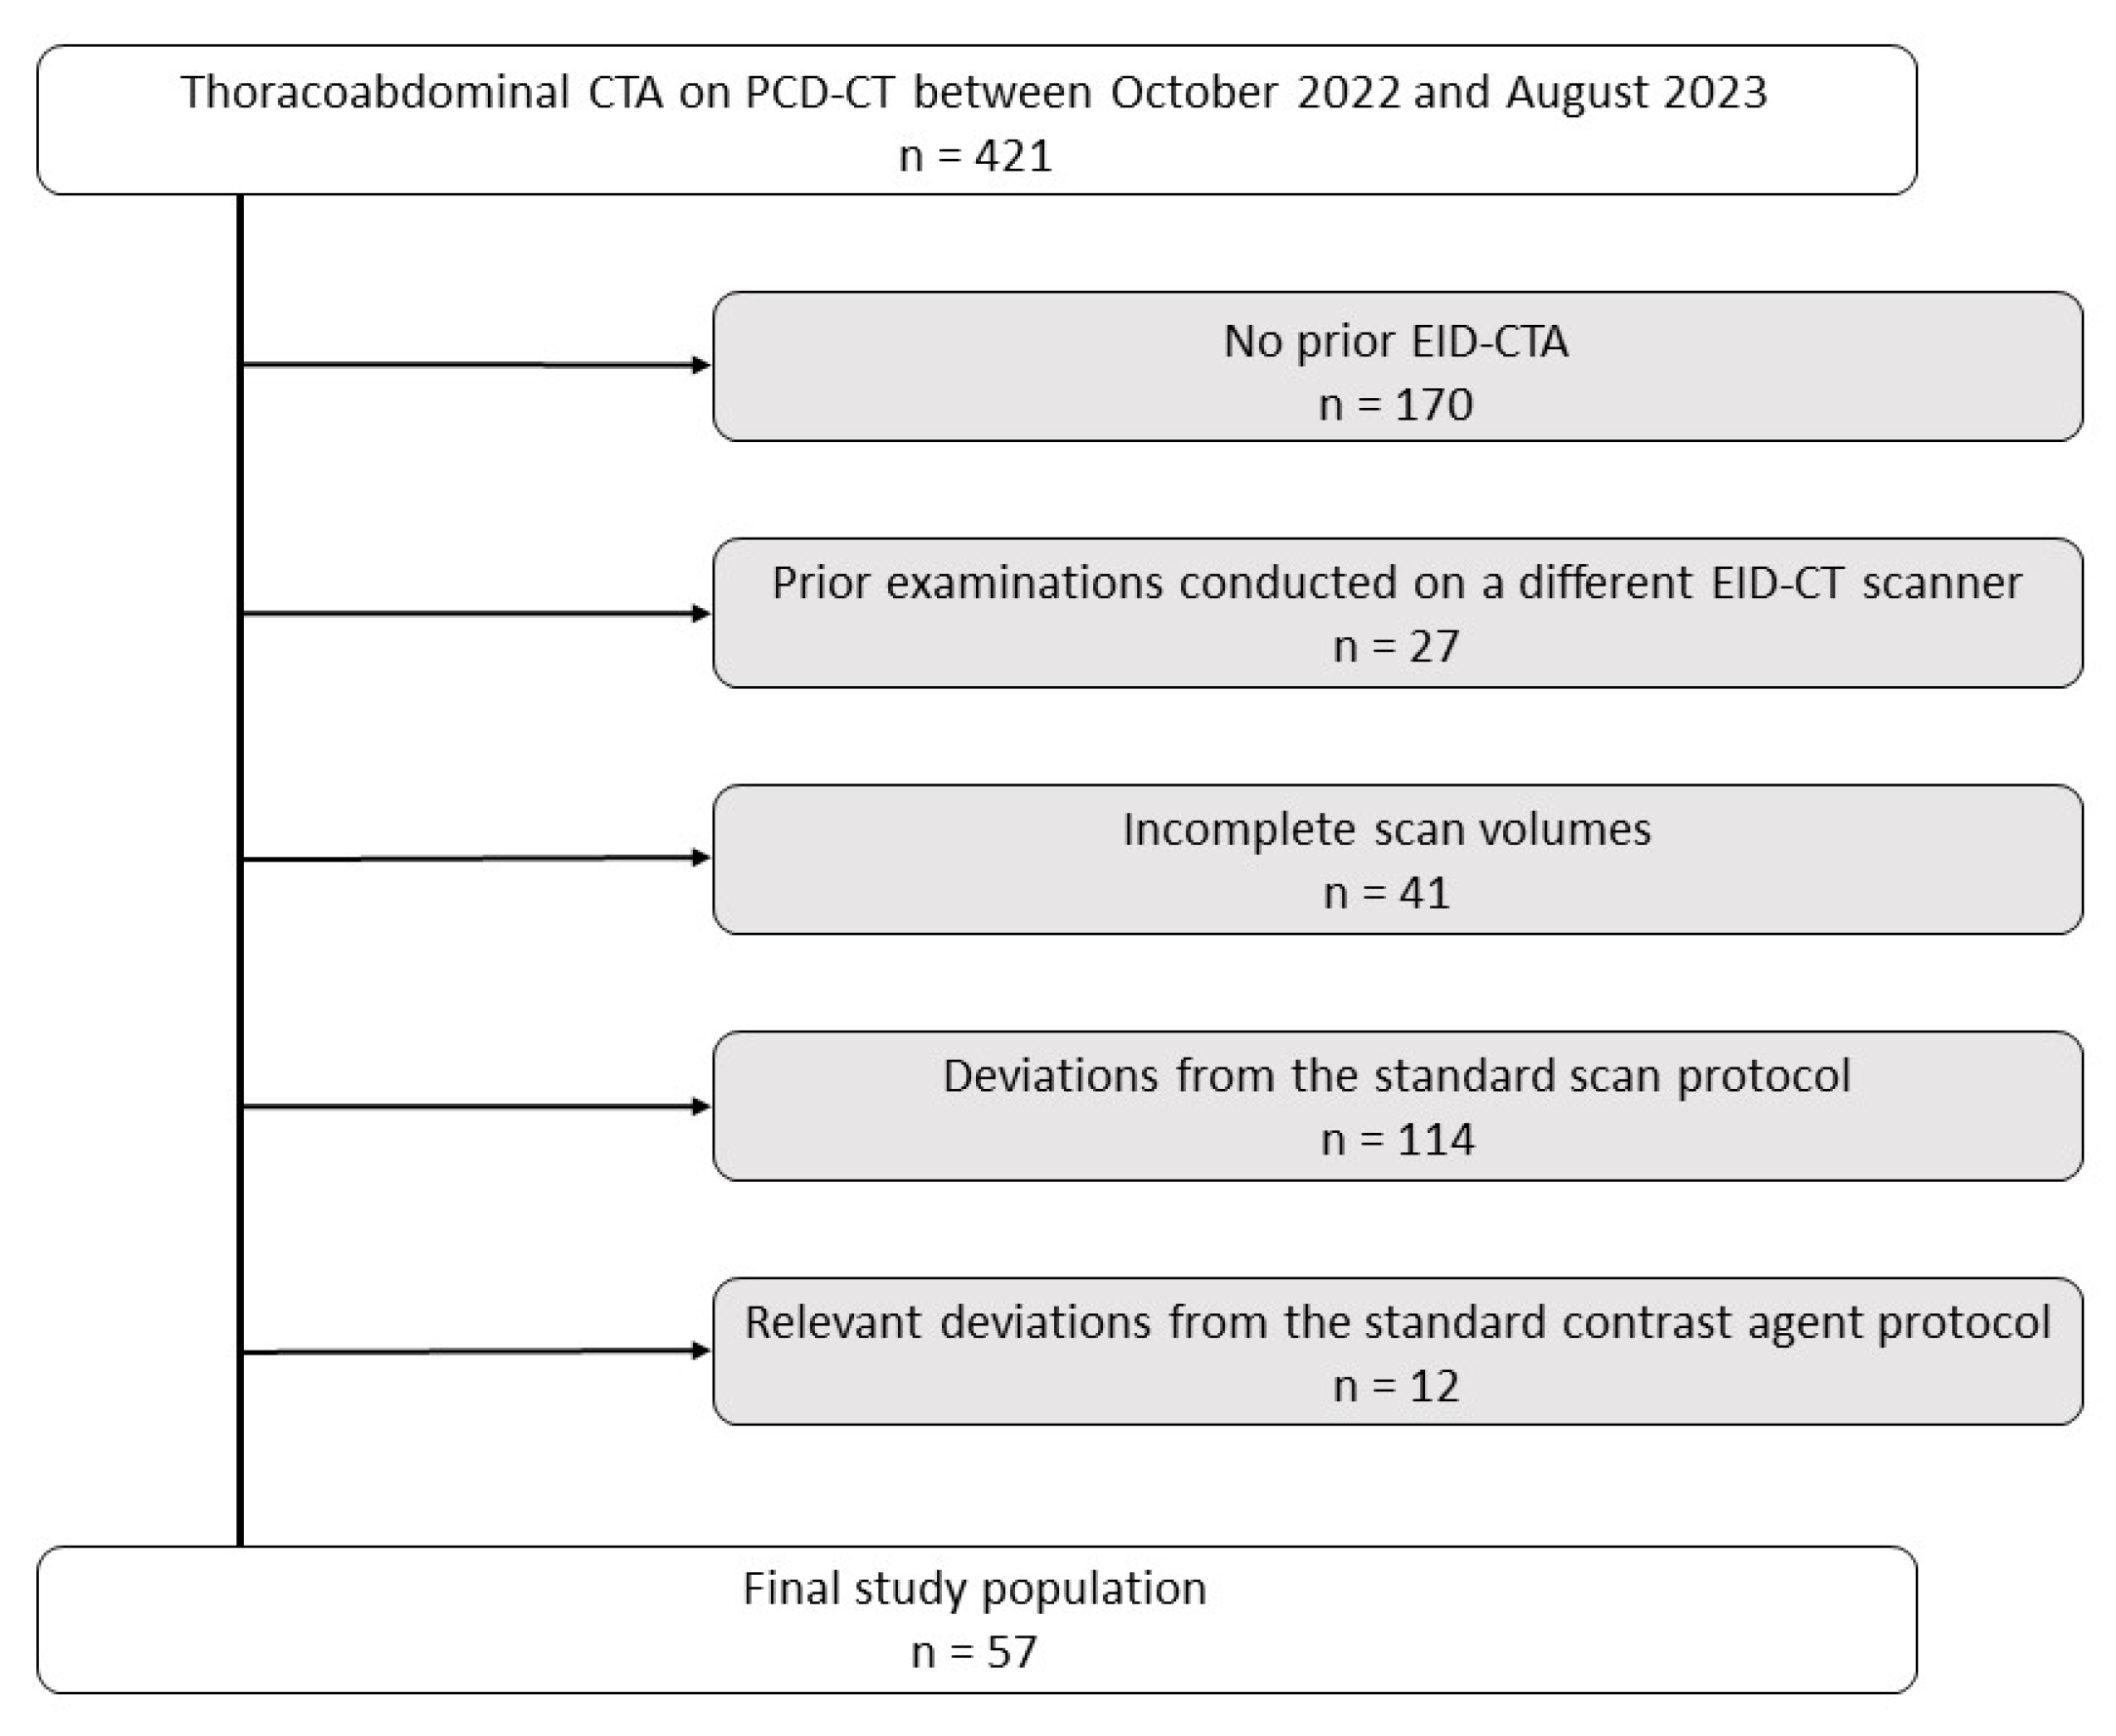

2.2. Study Protocol and Patient Population

3.1. Patient Characteristics and Radiation Dose